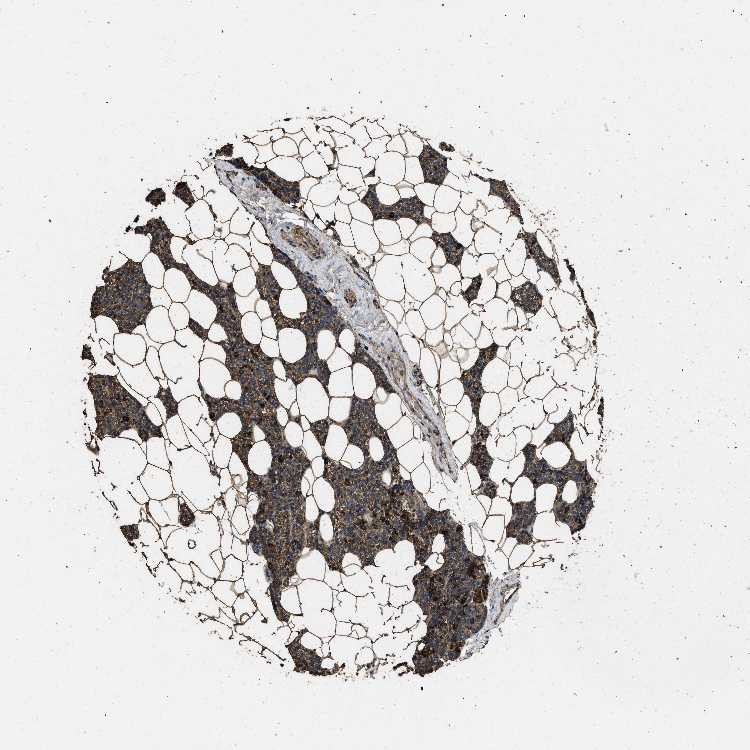

PARATHYROID GLAND - Antibody stainingi

Antibody staining in the annotated cell types in the current human tissue is reported as not detected, low, medium, or high, based on conventional immunohistochemistry profiling in selected tissues. This score is based on the combination of the staining intensity and fraction of stained cells.

Each image is clickable and will lead to virtual microscopy that enables deeper exploration of all samples and also displays staining intensity scores, fraction scores and subcellular localization as well as patient and tissue information for each sample.

Antibody CAB017847

Glandular cells High